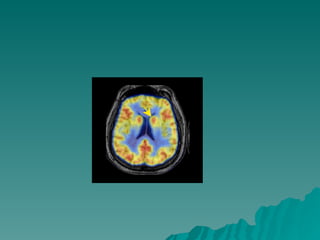

Cabeça do caudado Corte Transaxial

Cabeça do caudado Corte Sagital